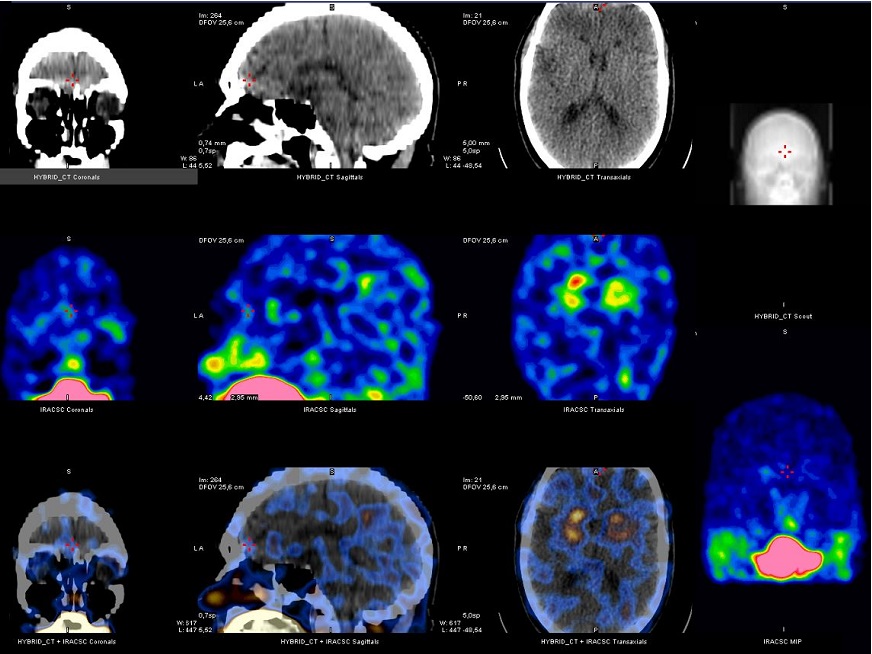

Rol del PET-CT en pacientes con Ataxia Cerebelosa